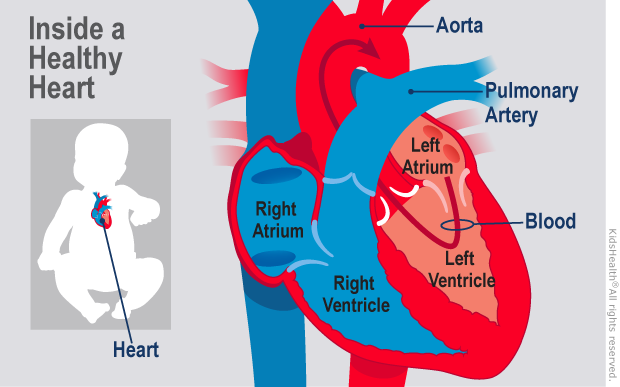

What is this PDA and why do the doctors want to close it

Text Patent Ductus Arteriosus PDA in Premature Infants

What is PDA in Newborn Babies

What is PDA in Newborn Babies

Patent Ductus Arteriosus PDA in the newborn

Patent Ductus Arteriosus PDA for Parents Nemours Kidshealth